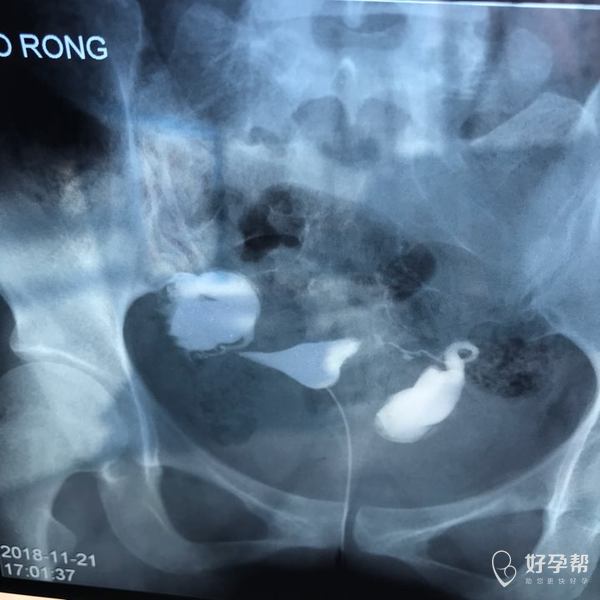

麻烦各位教授给我看看输卵管造影片子,谢谢了🙏

您好,输卵管堵塞,建议切除输卵管做试管,保守保守治疗没有多大意义,觉着我的回复对您有帮助记着帮忙点击采纳,谢谢!